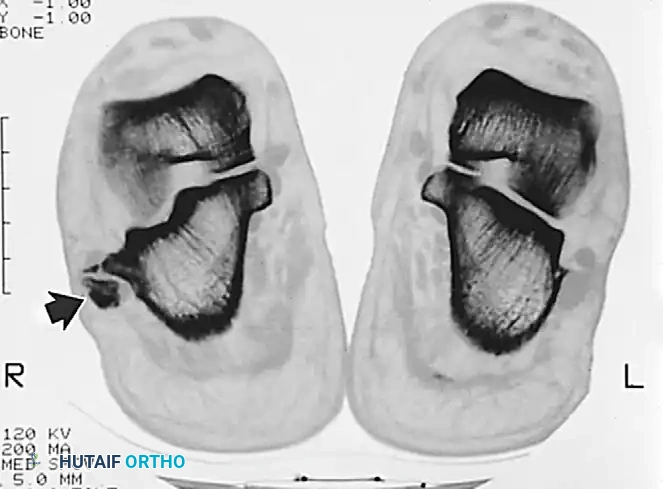

- Magnetic Resonance Imaging (MRI): The gold standard for evaluating tendon integrity, fluid within the tendon sheath (tenosynovitis), and the morphology of the retromalleolar groove.

Axial imaging demonstrating the relationship of the peroneal tendons within the retromalleolar groove.

Advanced axial imaging highlighting the peroneus longus and brevis pathology.